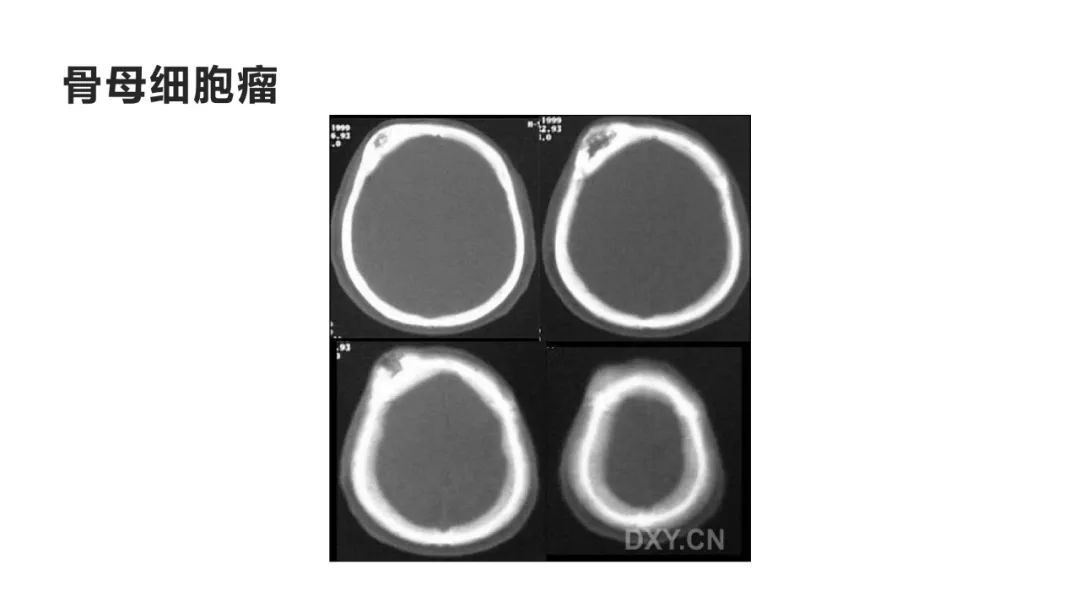

颅脑影像诊断基础知识讲座:颅骨病变